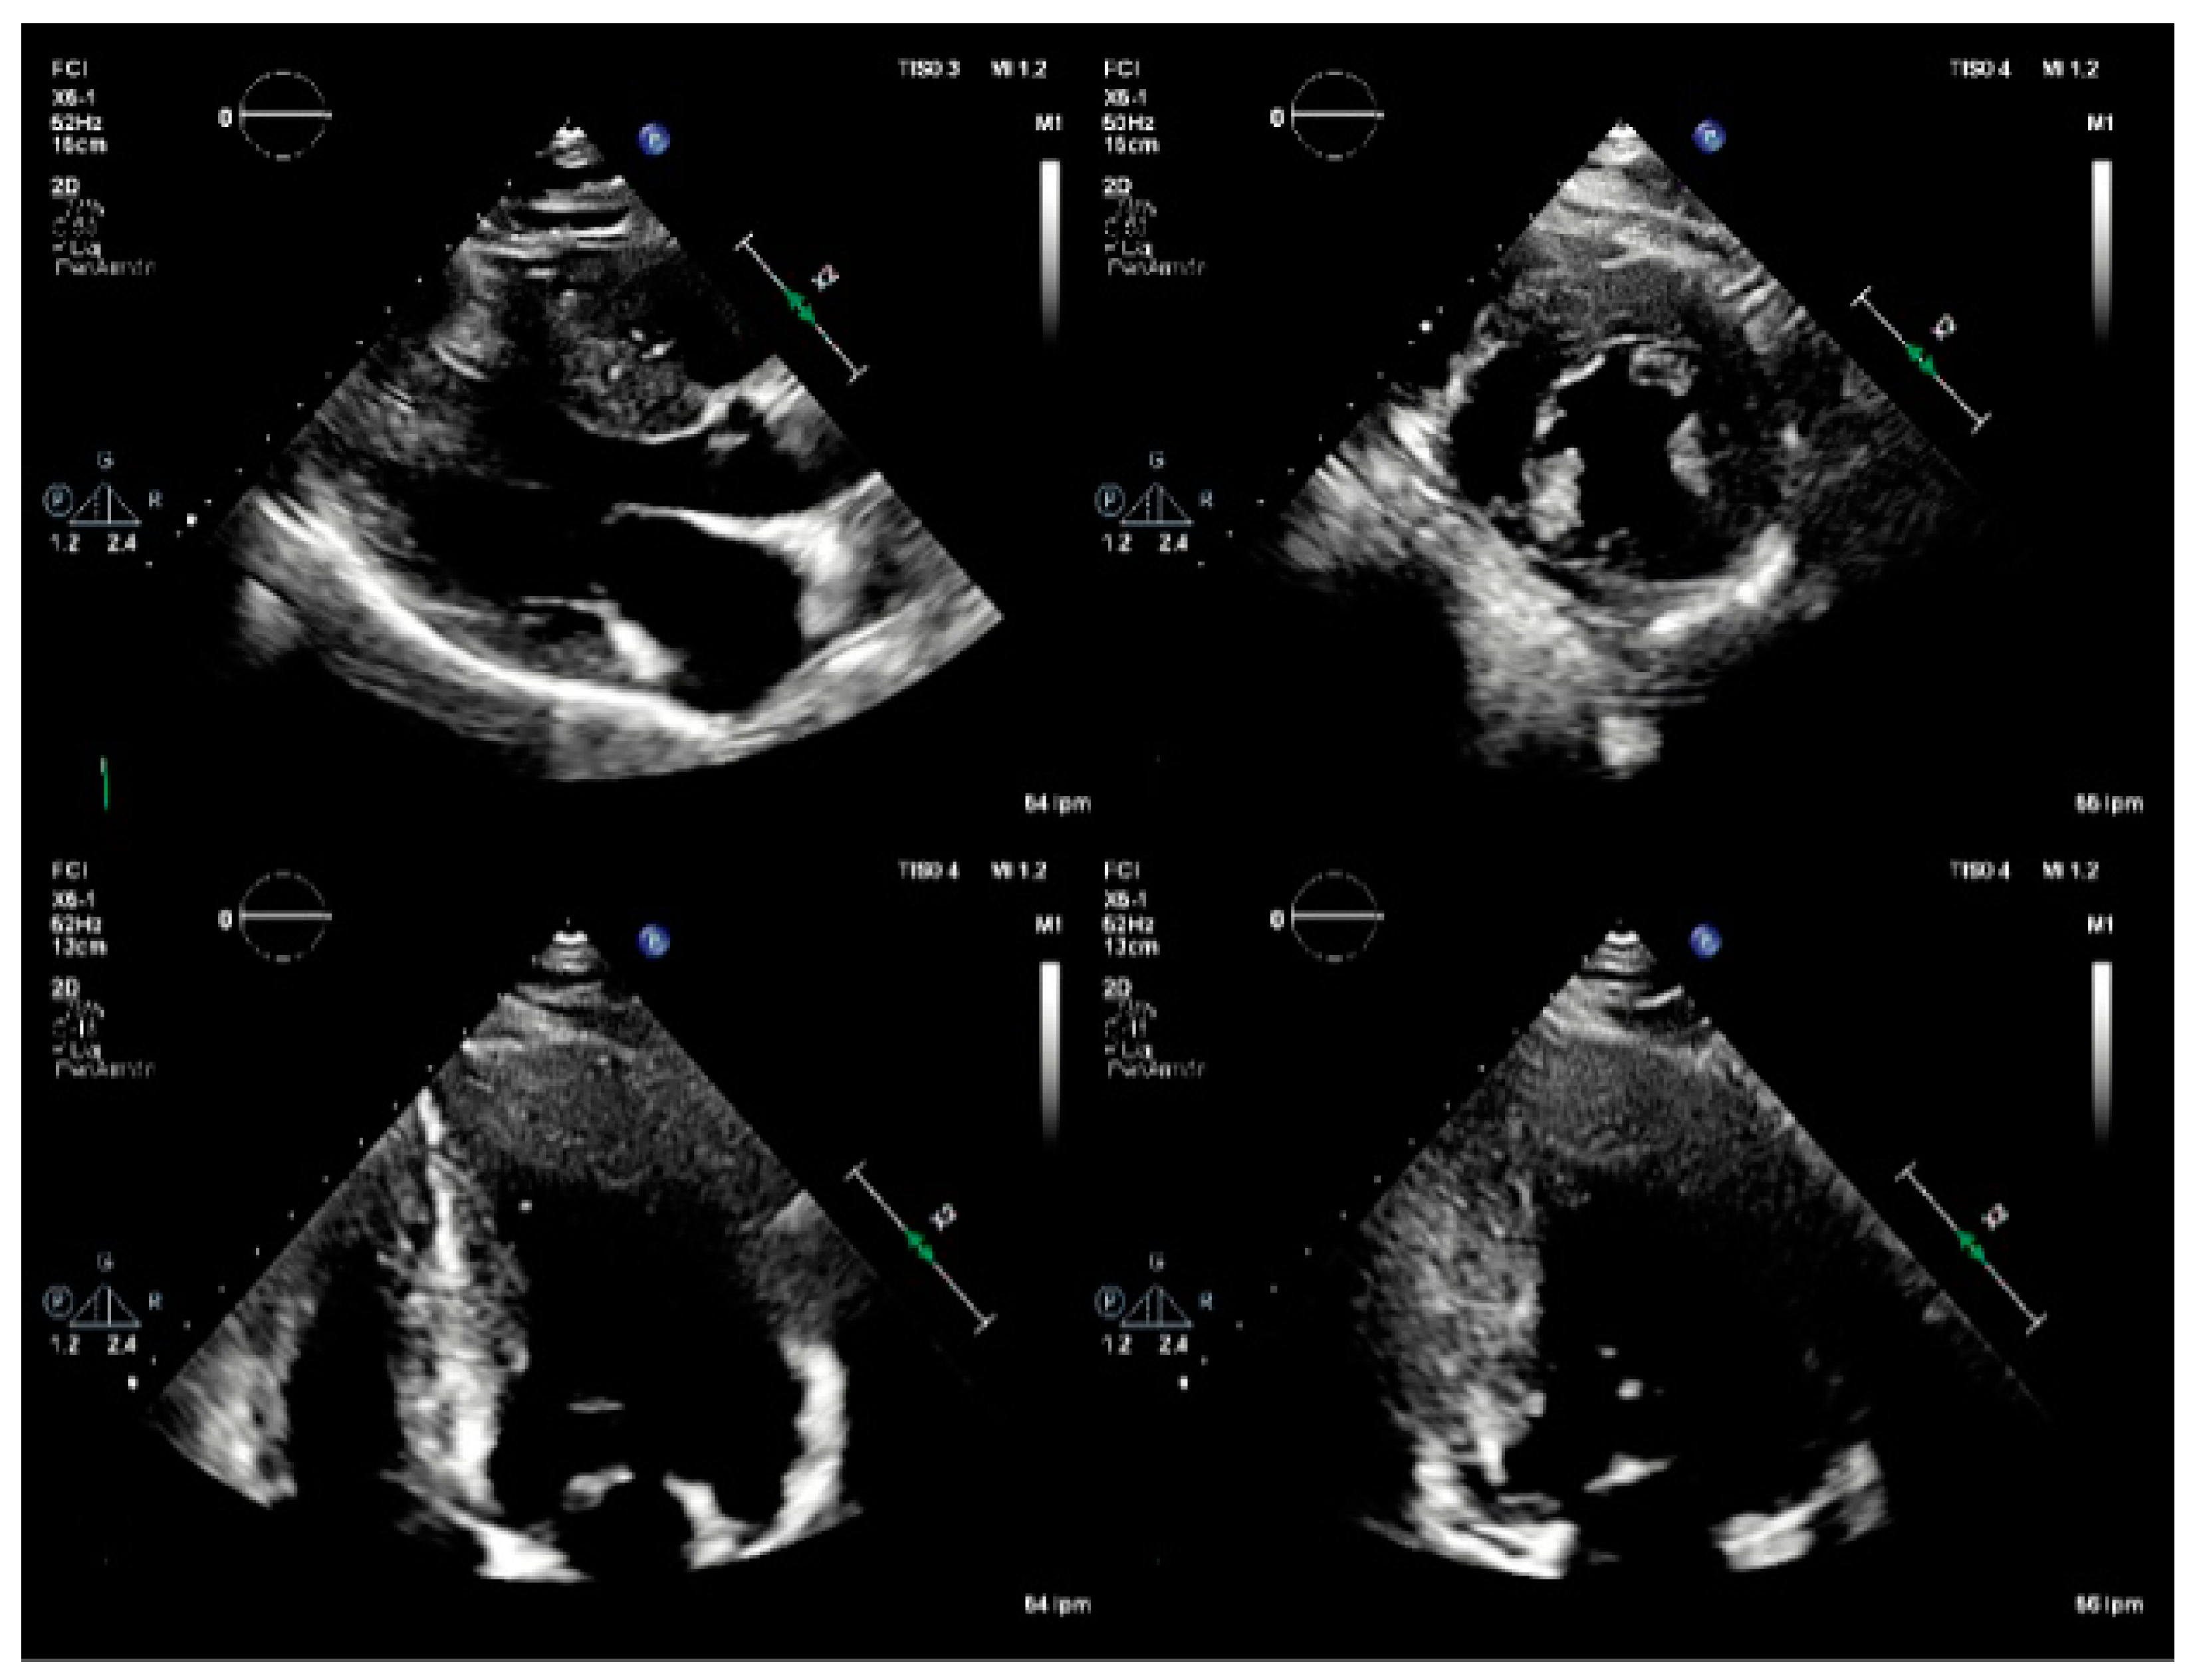

Figure 2. TTE: Parasternal long and short axis, apical 4-chamber, and apical 2-chamber views As. Basal inferoseptal thickness of 23 mm, and basal anteroseptal thickness of 21 mm. Normal LVEF (60%). Decreased LV global longitudinal strain, affecting mainly the inferoseptal wall, and the apical segments.

52-year-old man with history of hypertension since the age of 35 years, with no other significant personal or family history, under outpatient cardiology treatment, with regular blood pressure control, presented during follow-up studies exercise dyspnea. Studies were done, with an ECG showing left ventricular hypertrophy (LVH), and short PR interval (Figure 1). Transthoracic echocardiogram (TTE) evidenced increased end-diastolic thickness -basal infero-septal wall of 23 mm and basal anteroseptal wall of 21 mm (Figure 2), findings suggestive of HCM. For this reason, he was referred to our cardiac imaging laboratory, with indication of cardiac magnetic resonance, as a complementary study for HCM. CMR showed increased wall thickness, specially compromising the infero-septal wall, reaching 25 mm in the middle segment, without wall motion abnormalities, with normal left ventricle systolic function, LVEF: 64%. There was not systolic anterior motion of the mitral valve, and apical insertion of the papillary muscles was noted. Right ventricle wall thickness and systolic function was normal, RVEF: 72%. After contrast administration, patchy mid-wall late gadolinium enhancement (LGE) was seen in the inferoseptum, as well as in the basal and mid segments of the anterior, inferolateral and inferior wall. Findings suggestive of asymmetric septal HCM. At that time, our center did not have parametric mapping. With these findings, he was referred to our heart failure clinic for complementary studies. As part of the approach to the patient with hypertrophic phenotype, a next-generation sequencing (NGS) panel was requested.